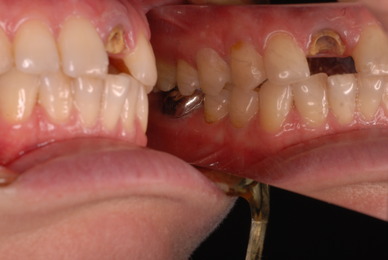

必ずばい菌が侵入しないようにしてばい菌である虫歯を除去します。

銀歯の下はばい菌だらけです。こういうのはよくあります。取り残しですね。![treatment_05[1]](https://livedoor.blogimg.jp/netdental/imgs/3/a/3ad019d0-s.jpg)